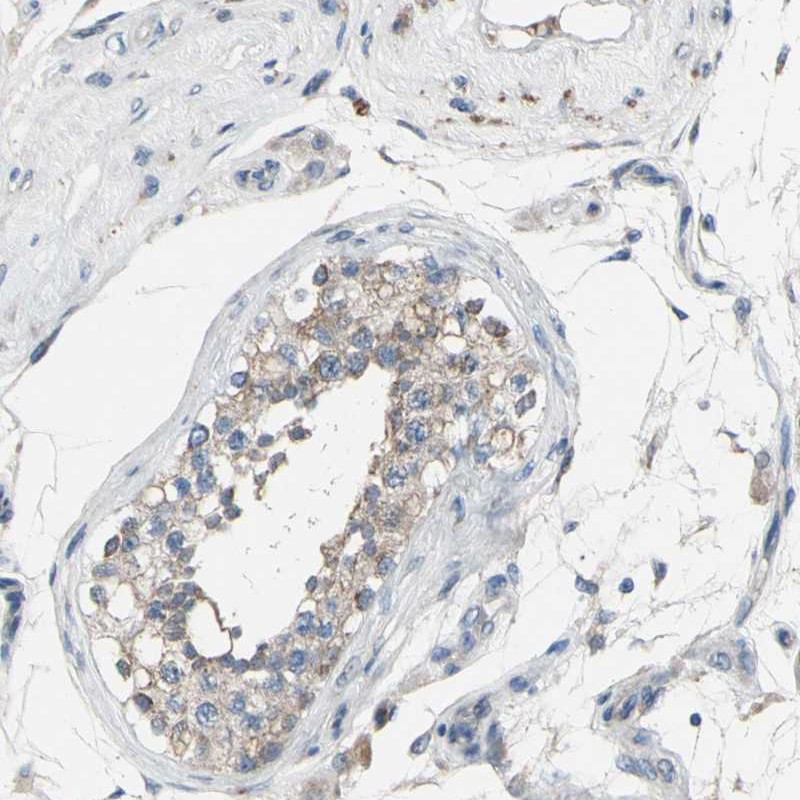

Immunohistochemistry analysis in human fallopian tube and testis tissues using Anti-GRAMD3 antibody. Corresponding GRAMD3 RNA-seq data are presented for the same tissues.